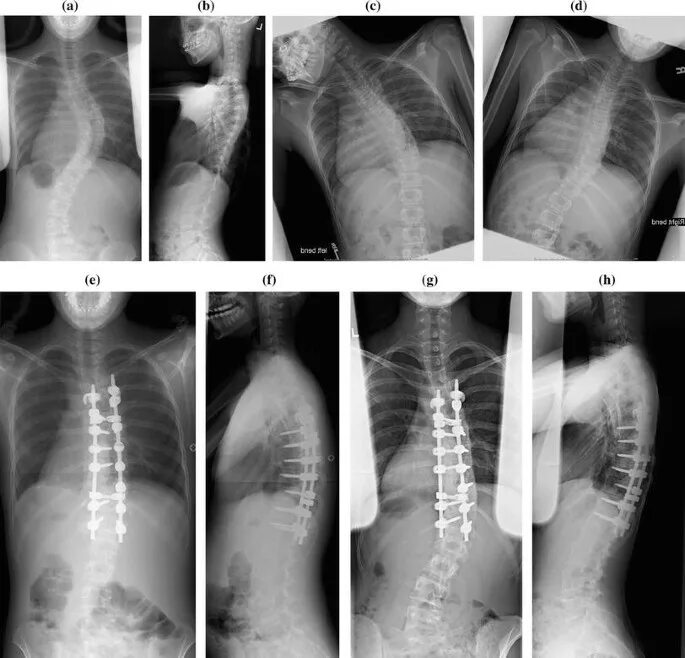

Pre operation